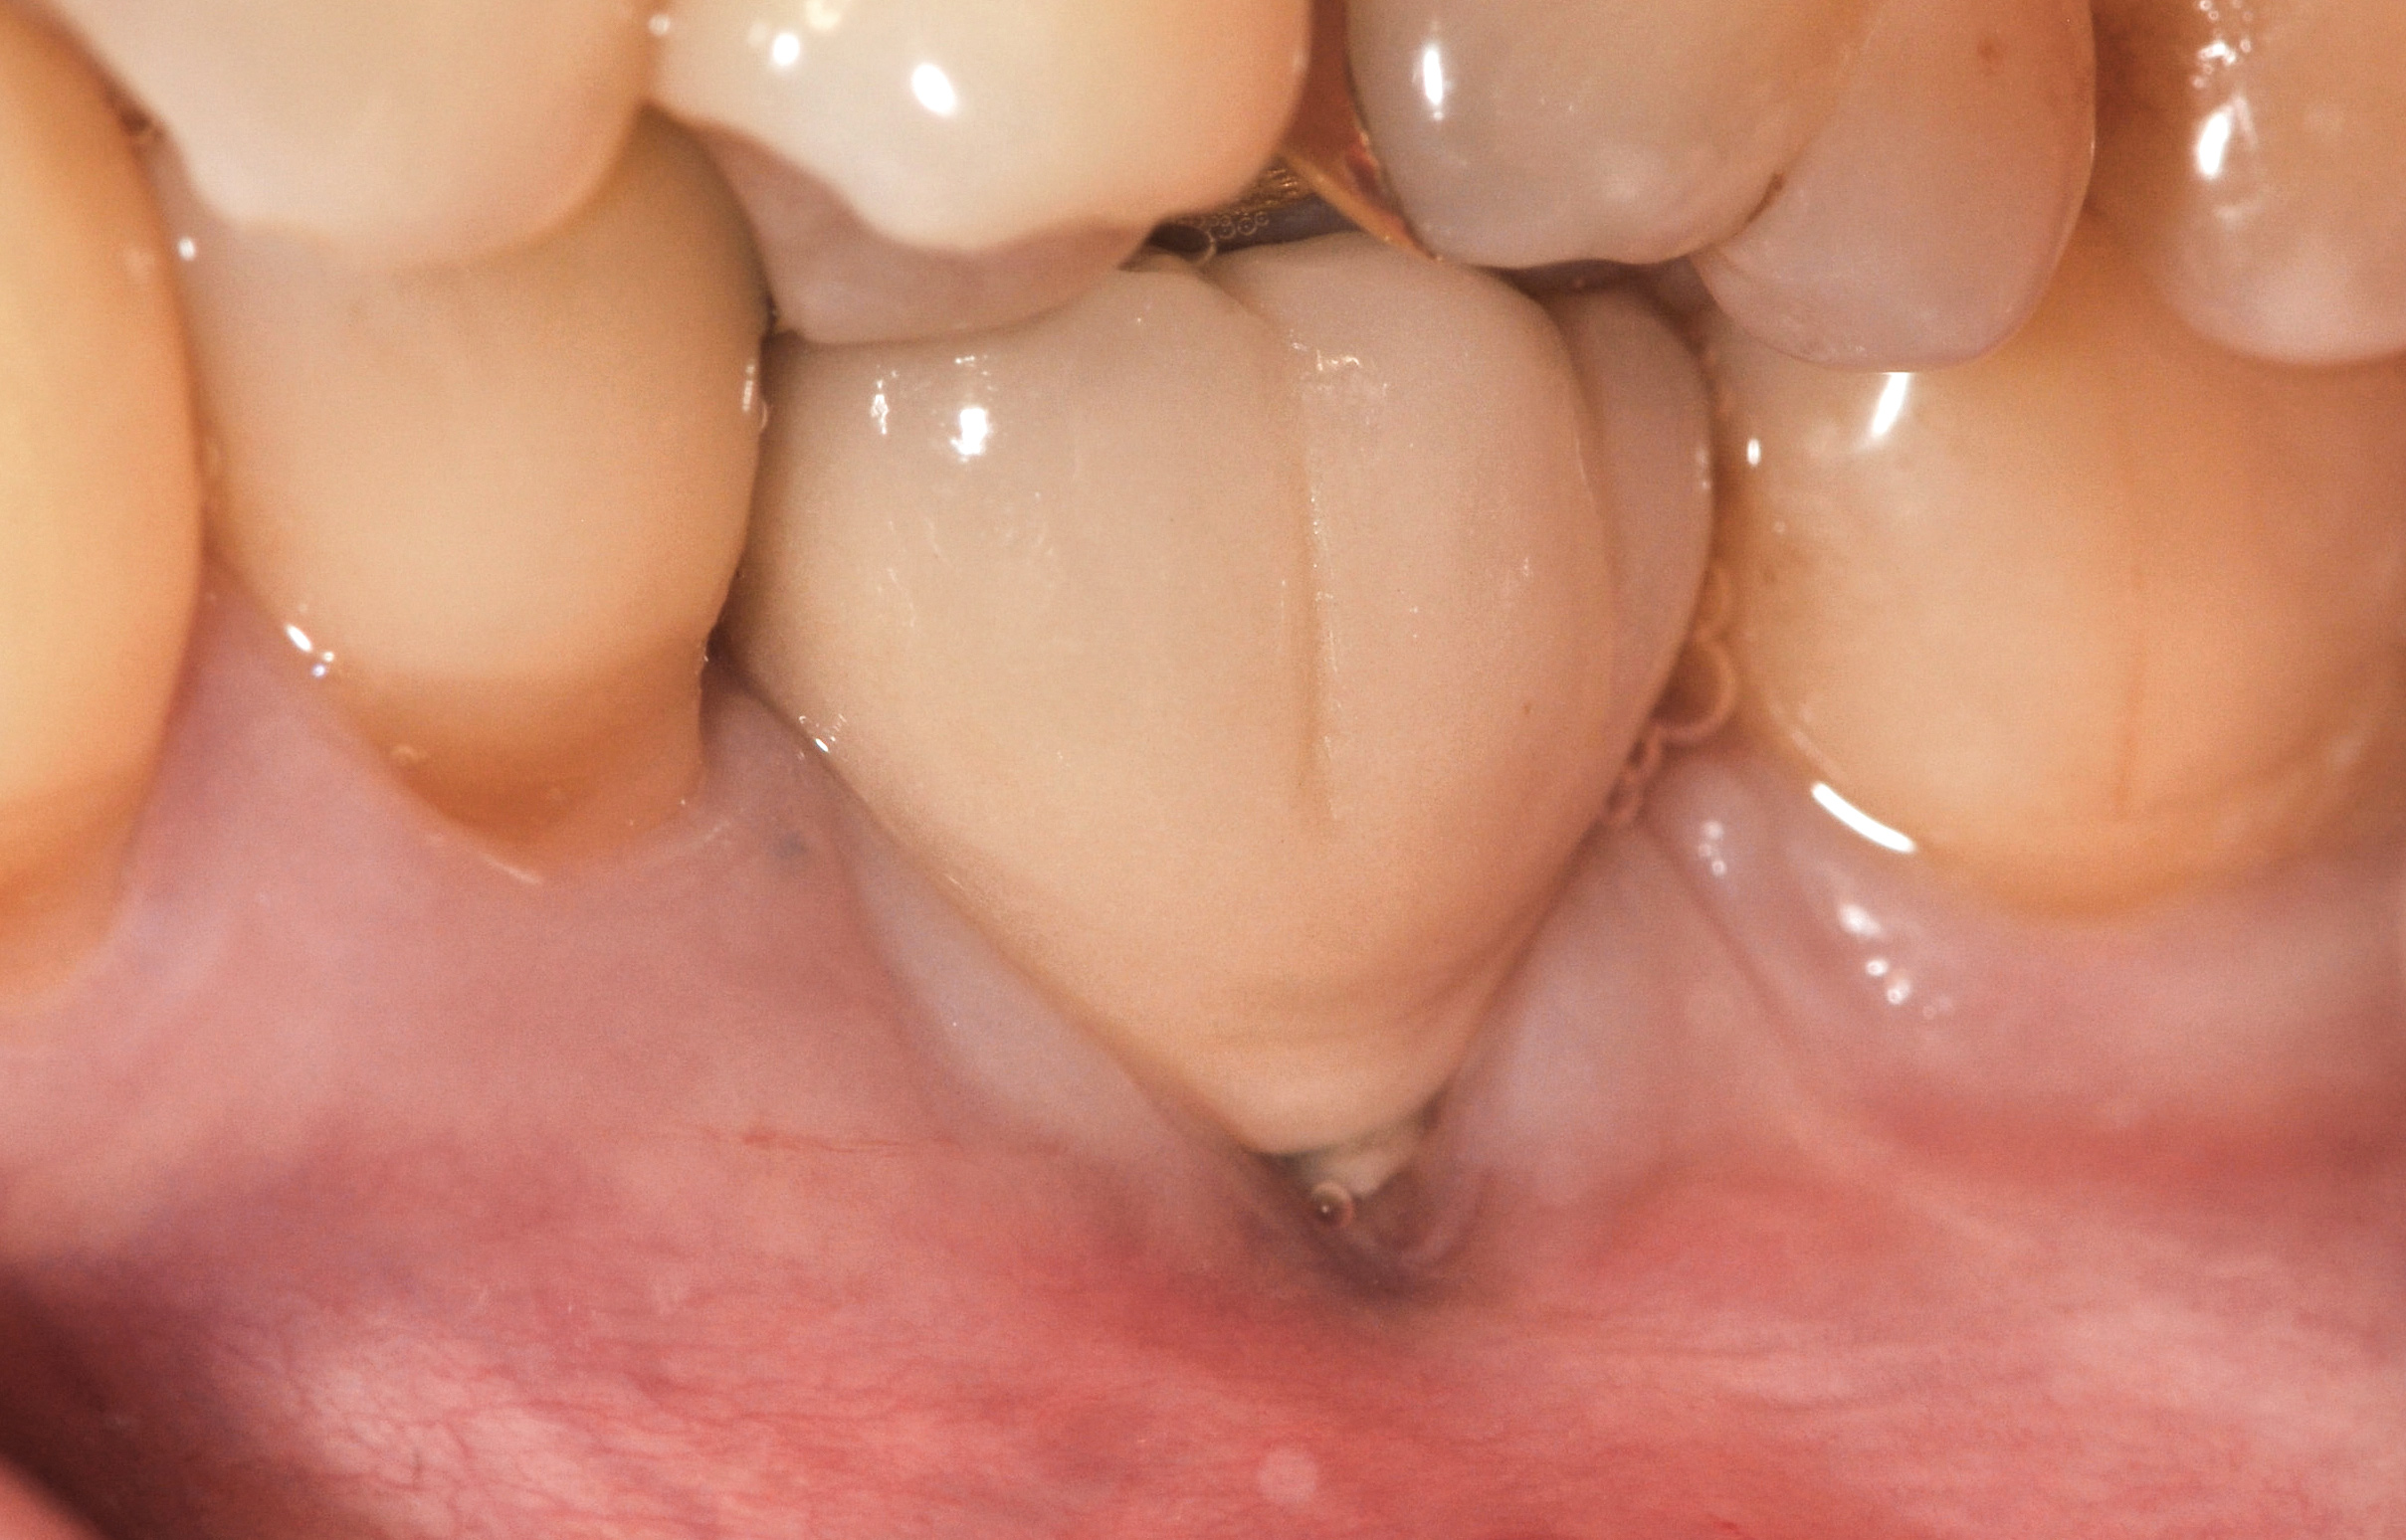

Fig 35. A transitional resin-bonded-retained (RBR) bridge that was tooth supported was placed to allow soft-tissue maturation.

Figure 35

Fig 36. Two weeks after RBR placement, the soft tissue did not adequately cover the implant. The problem was in poor implant angulation and proper depth to allow the soft tissues to cover over.

Figure 36